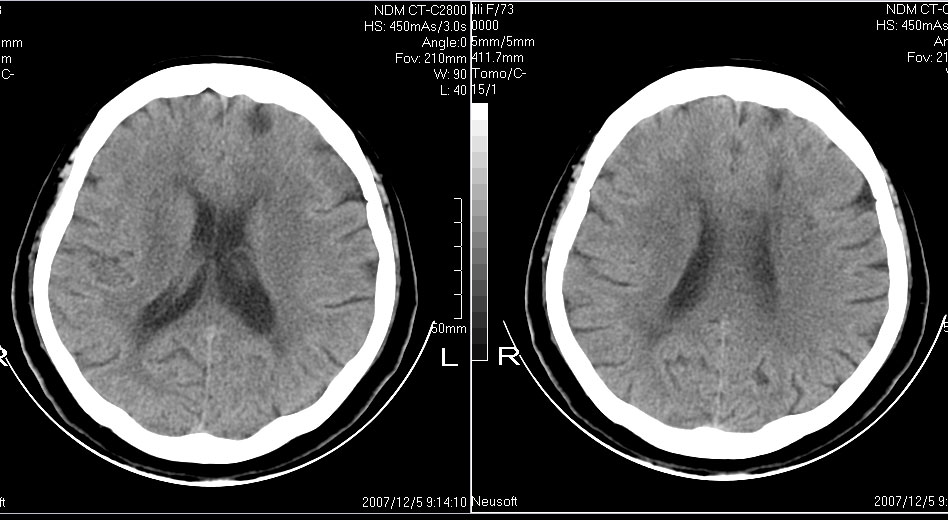

女,72,有高血压病史,突然寡言少语3日.

额叶多发梗塞,直回与人的情感有关

双侧基底节、左侧额叶 胼胝体膝部多发腔隙性脑梗塞。

1左额叶梗塞(多有情感障碍)2皮层下动脉硬化症